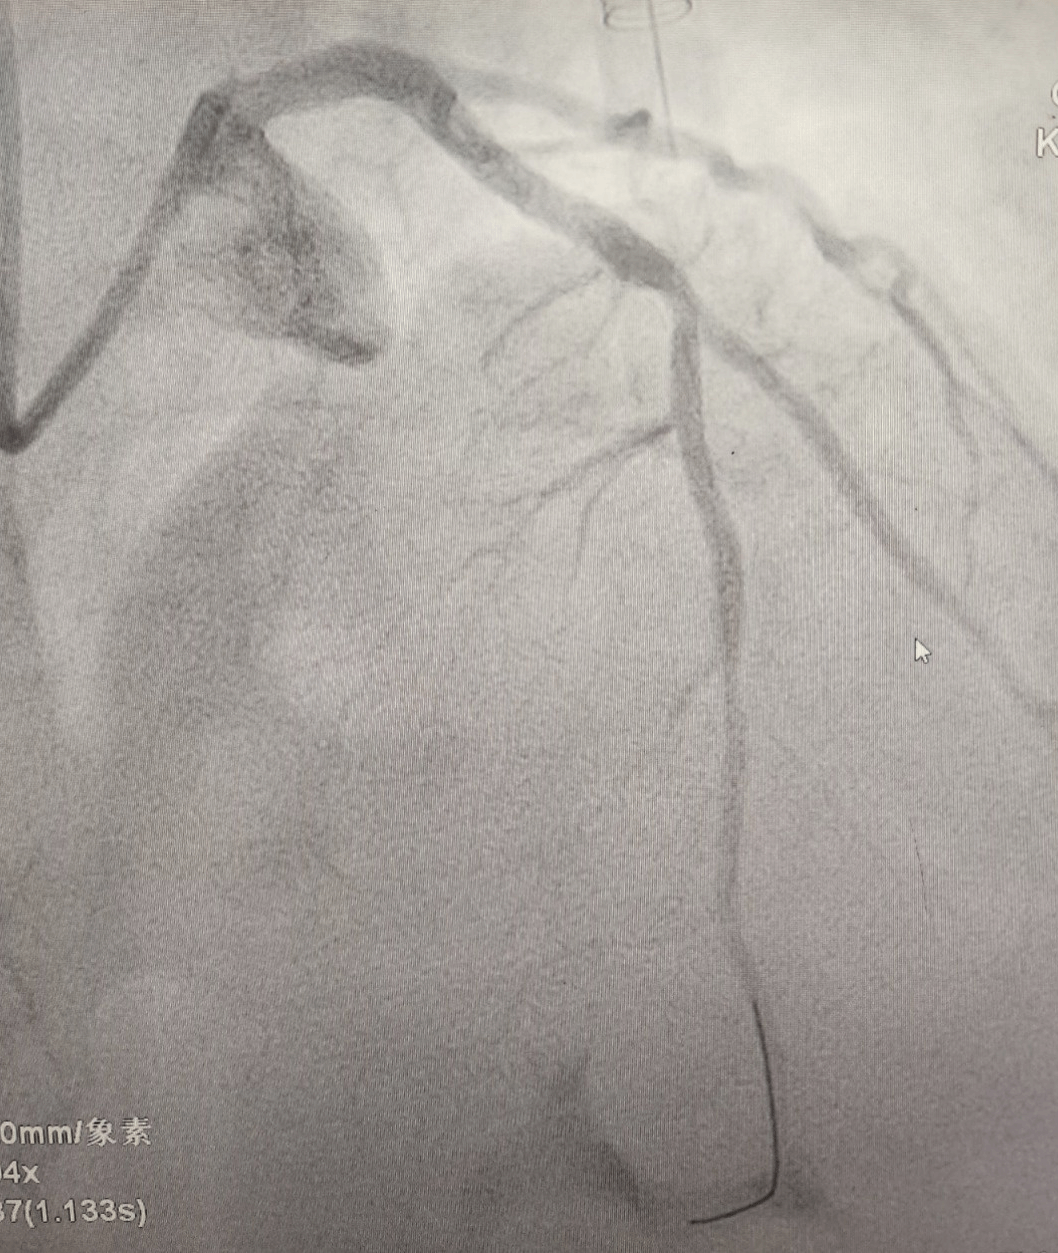

手术间内,铅衣加身,监护仪的滴答声与术者简短有力的口令声交织。冠脉造影精准锁定罪犯血管,导丝顺利通过,球囊精准扩张,一枚支架被准确植入闭塞段。患者进入导管室到血管开通 仅用时11分钟。术后,患者胸痛症状缓解,生命体征趋于平稳,被安全转运至CCU。

治疗前VS治疗后